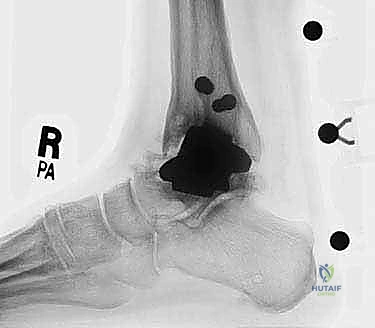

- الأشعة السينية مع تحميل الوزن (Weight-bearing X-rays): لتقييم الزوايا الميكانيكية وتحديد مدى هبوط المفصل أو وجود كسور في الكعب.

- التصوير المقطعي المحوسب (CT Scan): وهو الأداة الذهبية لتقييم "المخزون العظمي" (Bone Stock). يوضح بدقة حجم الأكياس العظمية ومقدار العظم المفقود الذي سيحتاج لترقيع.

من أعقد التحديات التي تواجه جراحي العظام هي حدوث كسور في الكعب الداخلي (Medial Malleolus) أو الخارجي (Lateral Malleolus) في وجود مفصل صناعي. تحدث هذه الكسور لعدة أسباب: